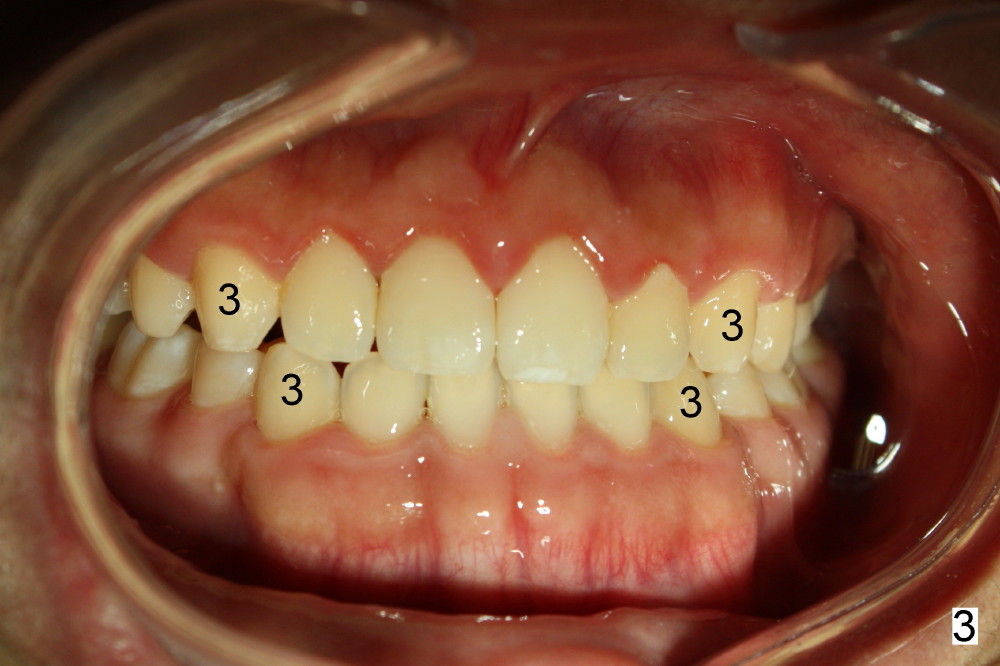

本文讨论如何与口腔专科医生打交道。十五岁男孩由妈妈带来诊所拔除四个智齿(图一:全景片;图二:侧面;图三:咬合正面(3:尖牙)),她说小孩刚刚完成矫正,如果不拔智齿,容易复发。应该拔吗?小孩有点早熟,发育几乎象成人。我该怎么处理?听口矫医生意见?